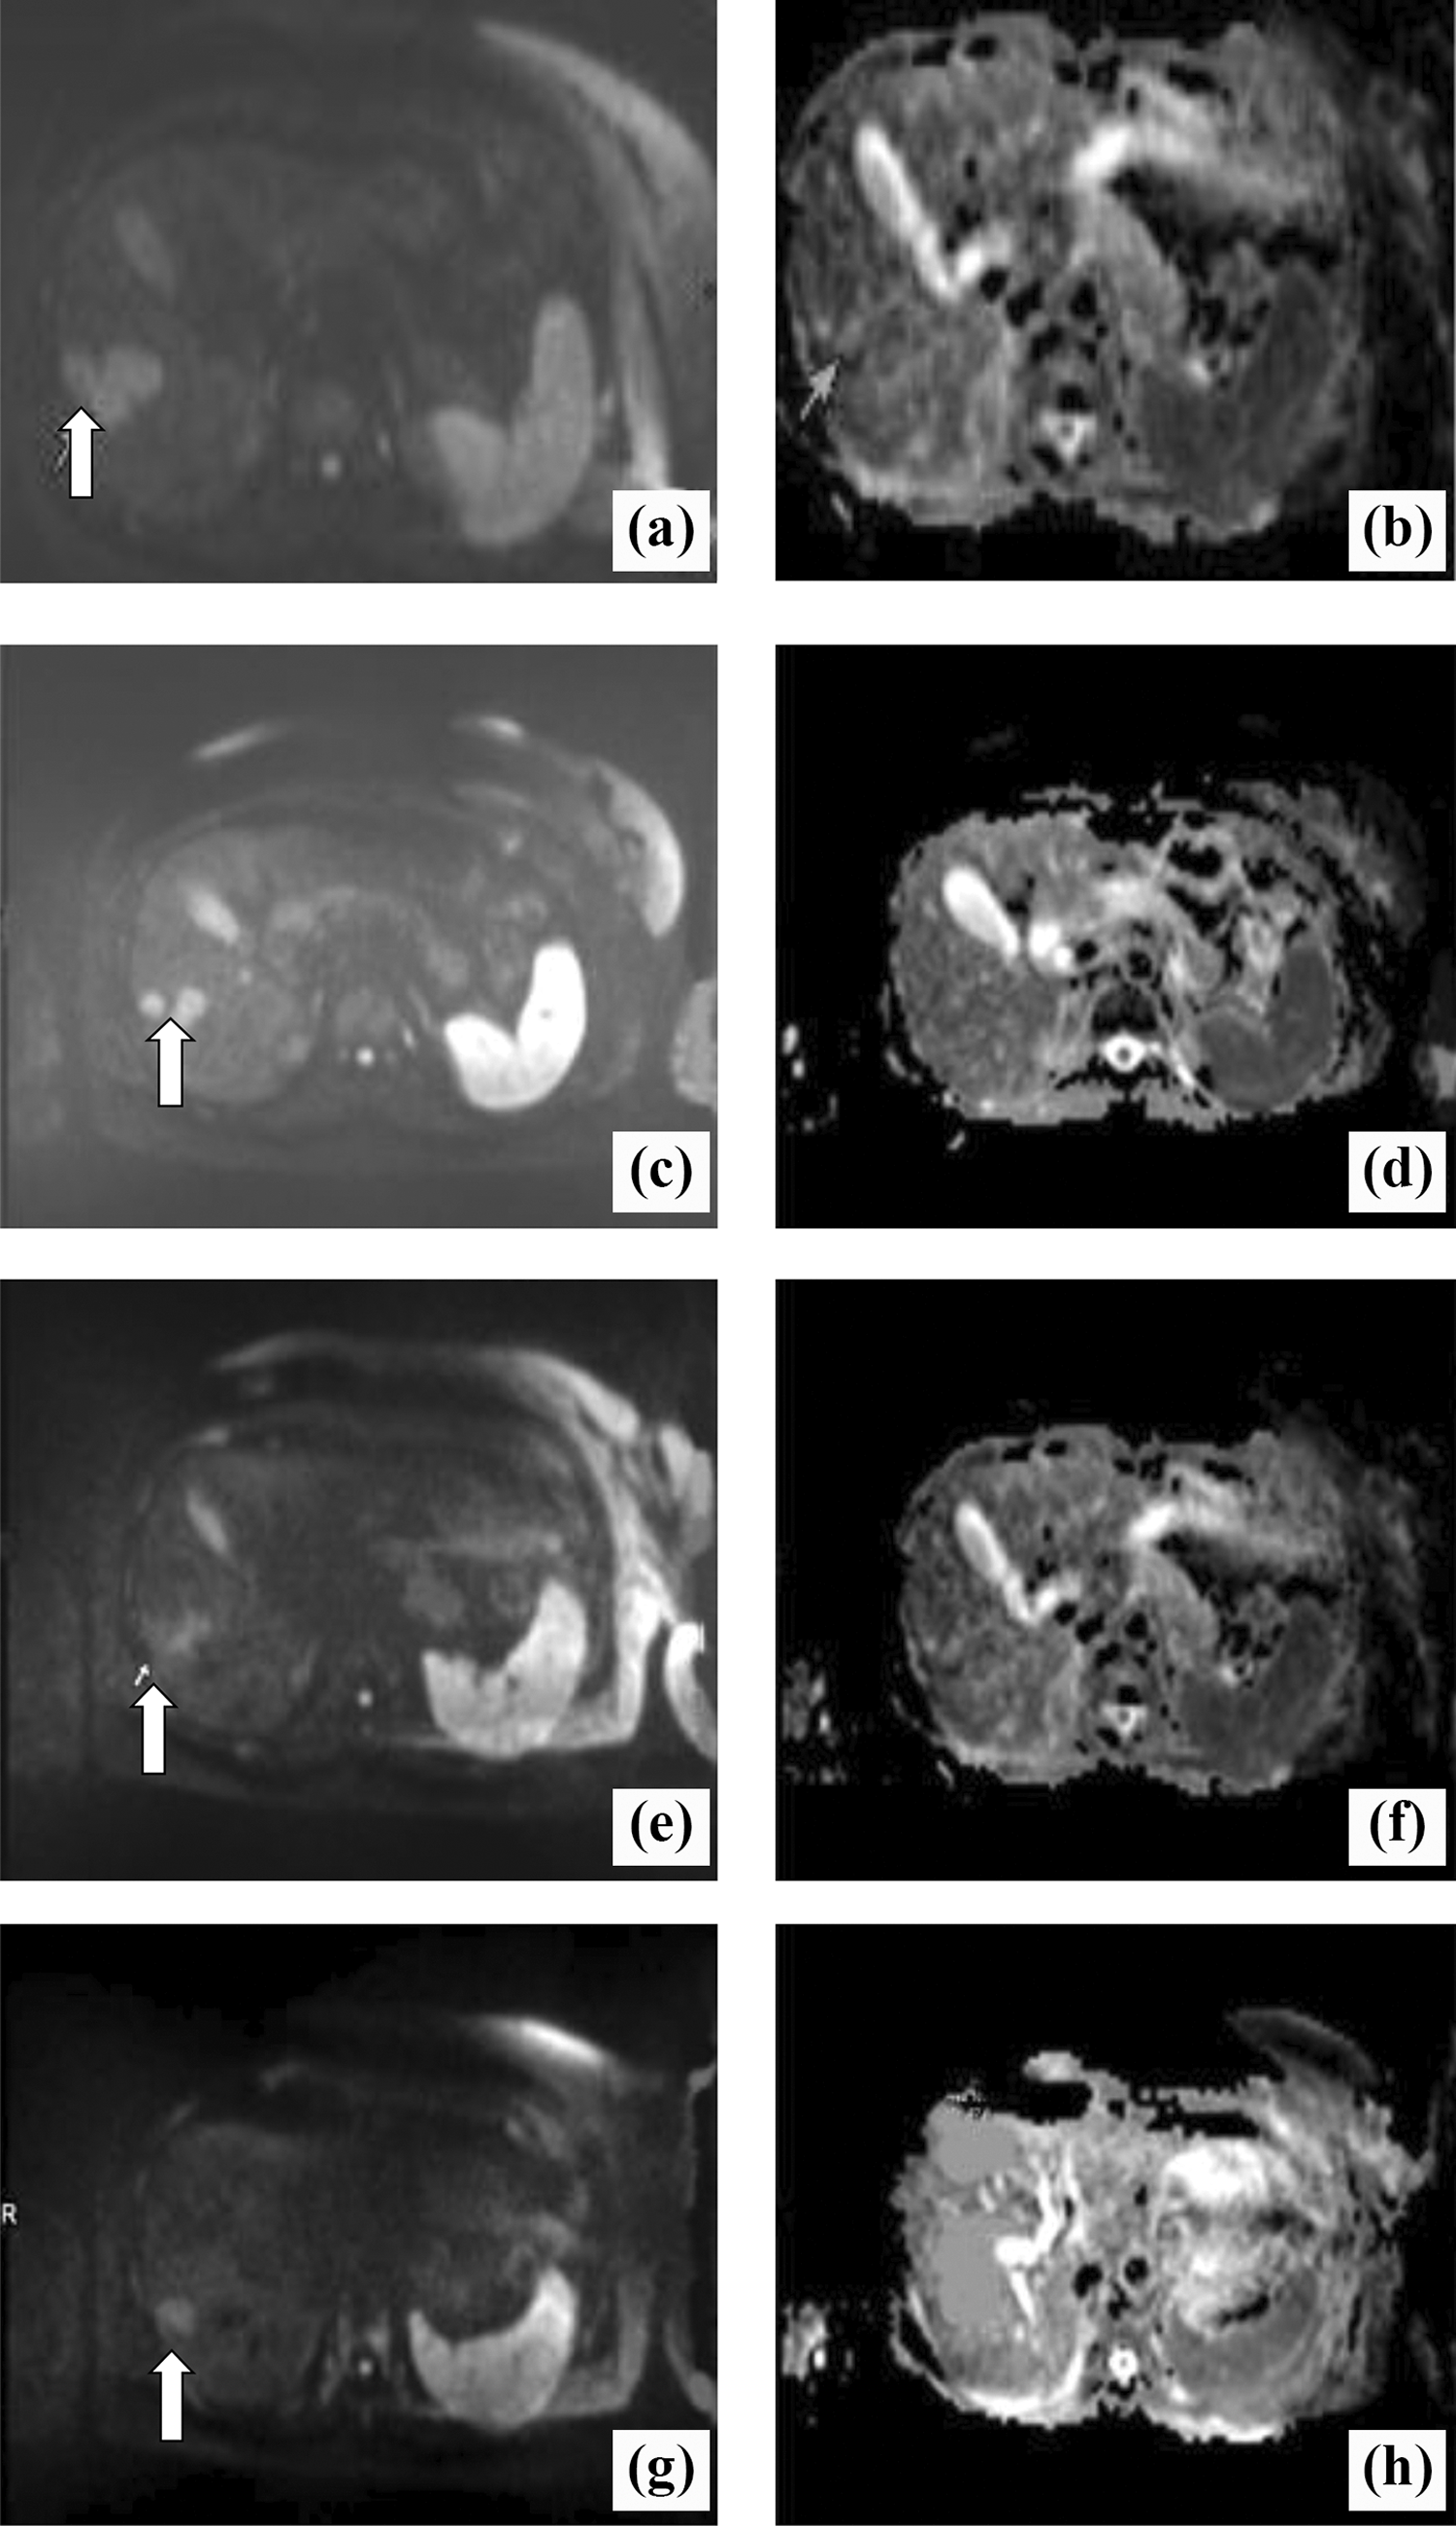

A 54-year-old patient with breast cancer liver metastases (BCLM) who received chemotherapy: (A and B) 3 to 4 days before chemotherapy; (C and D) 1 week after chemotherapy; (E and F) 2 weeks after chemotherapy; (G and H) 4 weeks after chemotherapy. In the diffusion-weighted magnetic resonance (DW-MR) images (A, C, E, F), the white arrow indicates the marker metastatic lesion located in the right lobe evaluated for dimensional and apparent diffusion coefficient (ADC) changes. Dimensional reduction is clearly visible at the early stage (C, E). The ADC maps show a consecutive increase in ADC(×10−3 mm2/s): 0.96 before chemotherapy (B), 1.07 after 1 week of chemotherapy (D), 1.38 after 2 weeks of chemotherapy (F), and 1.45 after 4 weeks of chemotherapy (H).

Analysis of ADC Changes

The mean ADC values of all the liver metastatic nodules at four different time points were 1.04 ± 0.24 × 10−3 mm2/s, 1.08 ± 0.24 × 10−3 mm2/s, 1.09 ± 0.25 × 10−3 mm2/s, and 1.07 ± 0.23 × 10−3 mm2/s, respectively, with no obvious increase after chemotherapy. The mean ADC values of lesions in R group at 4 different time points were 0.9 ± 0.16 × 10−3 mm2/s, 1.05 ± 0.12 × 10−3 mm2/s, 1.26 ± 0.12 × 10−3 mm2/s, and 1.33 ± 0.87 × 10−3 mm2/s, respectively. In addition, postchemotherapy ADC values were significantly higher than prechemotherapy ADC values, and the difference was statistically significant.